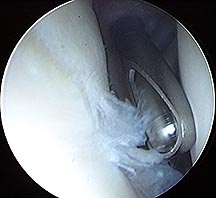

Arthroscopic Shaver used to remove frayed labral tissue

After removal of frayed tissue